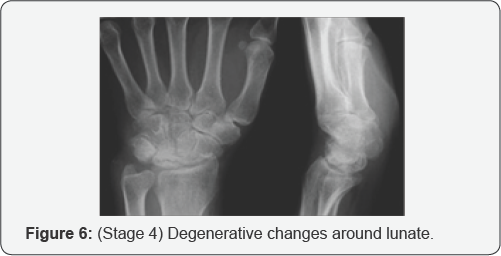

In early stages of this disease, the x-rays may be normal and other tests are needed to confirm the diagnosis. Most likely, the most reliable test to assess the blood supply of the lunate is Magnetic Resonance Imaging (MRI), CT scanning, specialized CT scanning and bone scan may also be used (Figure 2). The Stahl classification of Kienböck's disease, modified by Lichtman, is the most commonly used staging system and is useful in the treatment of Kienböck's disease (avascular necrosis of the lunate) [7]. This system divides the disease into four stages (Figures 3-6):

iv. Stage IV: degenerative changes around lunate (Figure 7).